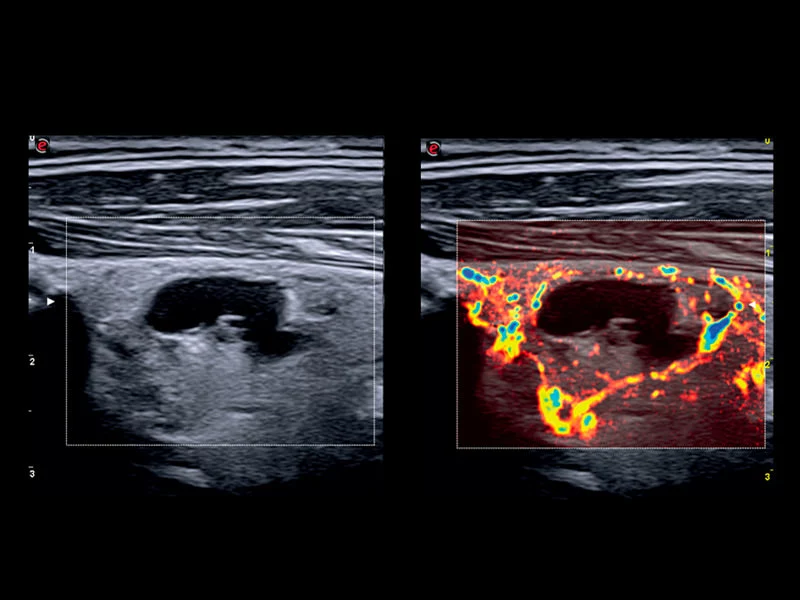

MyLab™9 Platform - High resolution imaging in testis

MyLab™9 Platform - High resolution imaging in testis

MyLab™9 Platform - XFlow in testis vascularization

MyLab™9 Platform - XFlow in testis vascularization